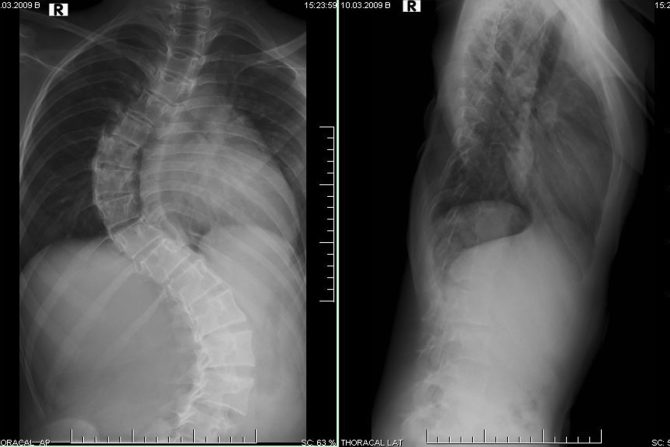

Bolovi u leđima i nogama su simptomi mnogih bolesti i na osnov njih ne može se utvrditi degenerativna skolioza. Deformitet se dijagnostikuje fizičkim pregledom, rendgenskim snimkom, magnetnom rezonancom. Na osnovu rendgenskog snimka i merenjem Cobbovog ugla može da se precizira stepen iskrivljenosti kičmenog stuba. Tačno izračunavanje Cobbovog ugla omogućava lekarima da odrede težinu deformiteta i na osnovu svih parametara utvrde najbolje načine lečenja.